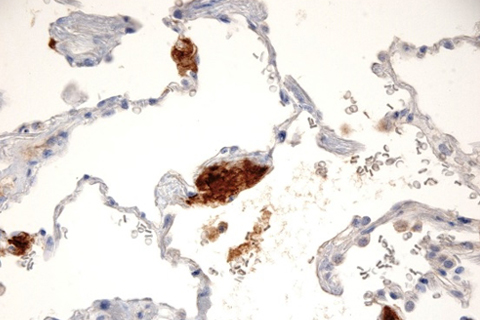

Pulmonary amyloidosis transthyretin stain